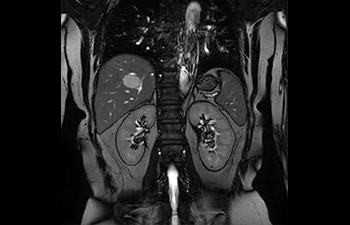

• Es una innovadora técnica de aceleración que no solo permite agilizar las secuencias, sino todo el estudio. • Implementación especial con la que las exploraciones en 2D y 3D pueden llegar a ser hasta un 50% más rápidas con una calidad de imagen prácticamente equivalente.1

• Se puede usar con todos los contrastes y con todas las regiones anatomías.

con Compressed SENSE